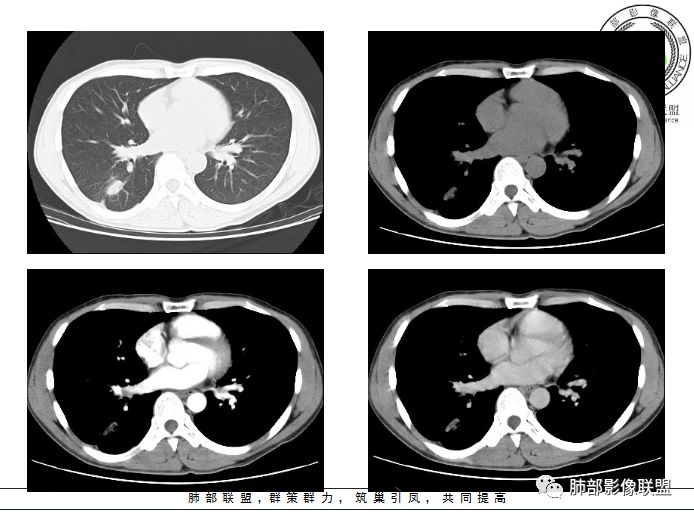

小赵:青年男性,慢性咳嗽,低热,血沉略快。右肺类圆形肿块,密度偏低,周围见条索,较低层面似见卫星灶,邻近胸膜增厚。增强扫描薄膜样强化。综合考虑结核可能

市医院-时建文:青年男性,慢性咳嗽,低热,右肺类圆形肿块,密度偏低,周围见条索,血管贴边,邻近胸膜增厚。结核?psp?

一米阳光:右肺下叶后基底段长圆形病变,边缘清晰,中心部密度减低,增强病变前缘见血管影,略环形强化,病变周围见点状及索条影,结合年轻病史,考虑结核

甄德强:右肺下叶结节影,边缘见多条软毛刺,包膜样强化,卫星病灶,考虑结核,不除外合并曲霉

大雄:似乎是支气管相连续,无强化,平扫似有高密度,考虑支扩粘液栓(曲霉所致)

小微:青年男性,慢性咳嗽,低热,血沉快。右肺类圆形肿块,其内见低密度影,周围见条索,较低层面似见卫星灶,邻近胸膜增厚。增强扫描薄膜样强化,其内为低密度坏死。综合考虑结核可能。有血管贴边,待除外PSP

弹指之间:1. 青年男性,慢性咳嗽,低热,血沉快。2. 右肺下叶类圆形肿块,周围见条索,较低层面似见卫星灶,邻近胸膜增厚。增强后见轻度延迟强化,见血管贴边征,肺门侧见小淋巴结影(肺静脉起始处肿大淋巴结不确切);3. 右肺下叶体积未见缩小,局部支气管不扩张,无钙化;综合考虑结核可能,PSP和小细胞肺癌待排

男,34岁,主诉:间断性咳嗽伴右胸反复不适半年;现病史:右胸不适,深呼吸加重,伴轻度咳嗽、低热;

青年男性、病史半年,低热;

右肺下叶囊性病变,边缘光滑,薄环状强化,内壁较光滑

血管贴边

周围多发长索条

远端有斑片状条带状高密度影,周围肺气肿

附近胸膜增厚,内有血管影